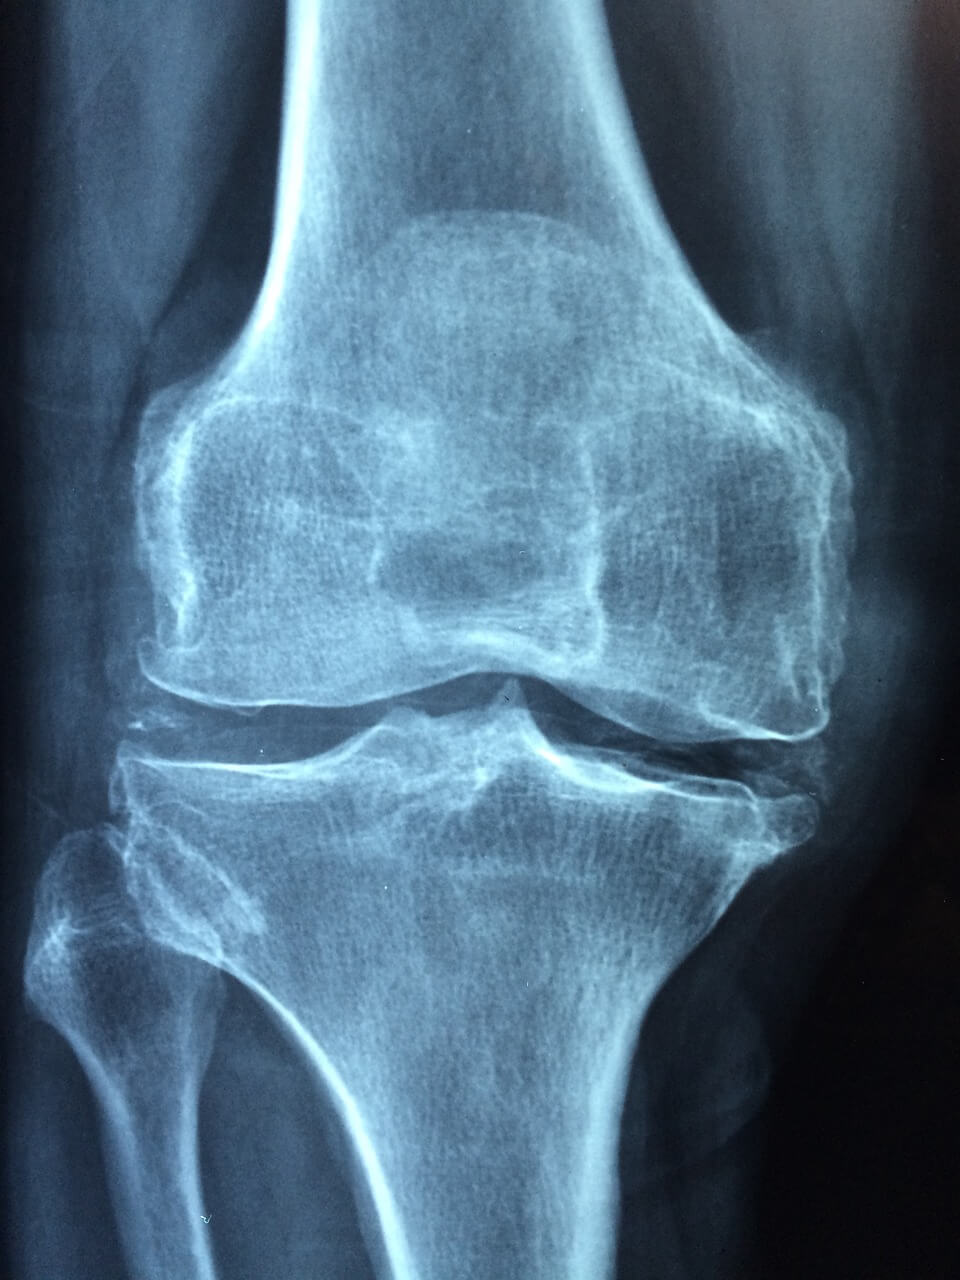

무릎 연골 손상의 증상은 다양할 수 있습니다. 주요 증상으로는 무릎 통증, 무릎 부기, 관절 움직임의 제한, 무릎에서 끈적거리는 느낌 등이 있습니다. 무릎 관절 연골 부근의 통증 증상은 활동 시 더욱 두드러질 수 있으며 불편함이 심하다면 의사와 상담하시는 편이 좋습니다.

무릎 연골 손상의 주사 치료는 꼭 의사와 상담한 후 진행해야 합니다. 치료 전에 주의사항과 치료 계획을 정확하게 이해하고 의사의 지시를 따르는 것이 중요합니다. 무릎 연골 손상의 정확한 원인과 증상을 파악하여 적절한 치료 방법을 선택하는 것이 빠른 회복을 위한 핵심입니다.

무릎 연골 관절과 연골은 시기를 놓치면 회복이 어려운 신체부위로 적절한 시기를 놓치지 않고 치료를 받는 것이 중요합니다. 증상을 꼭 가볍게 여기고 지나치지 마시고 가까운 병원에 방문하셔서 연골이 더이상 손상되지 않도록 조치를 취하시는 걸 권해드립니다.